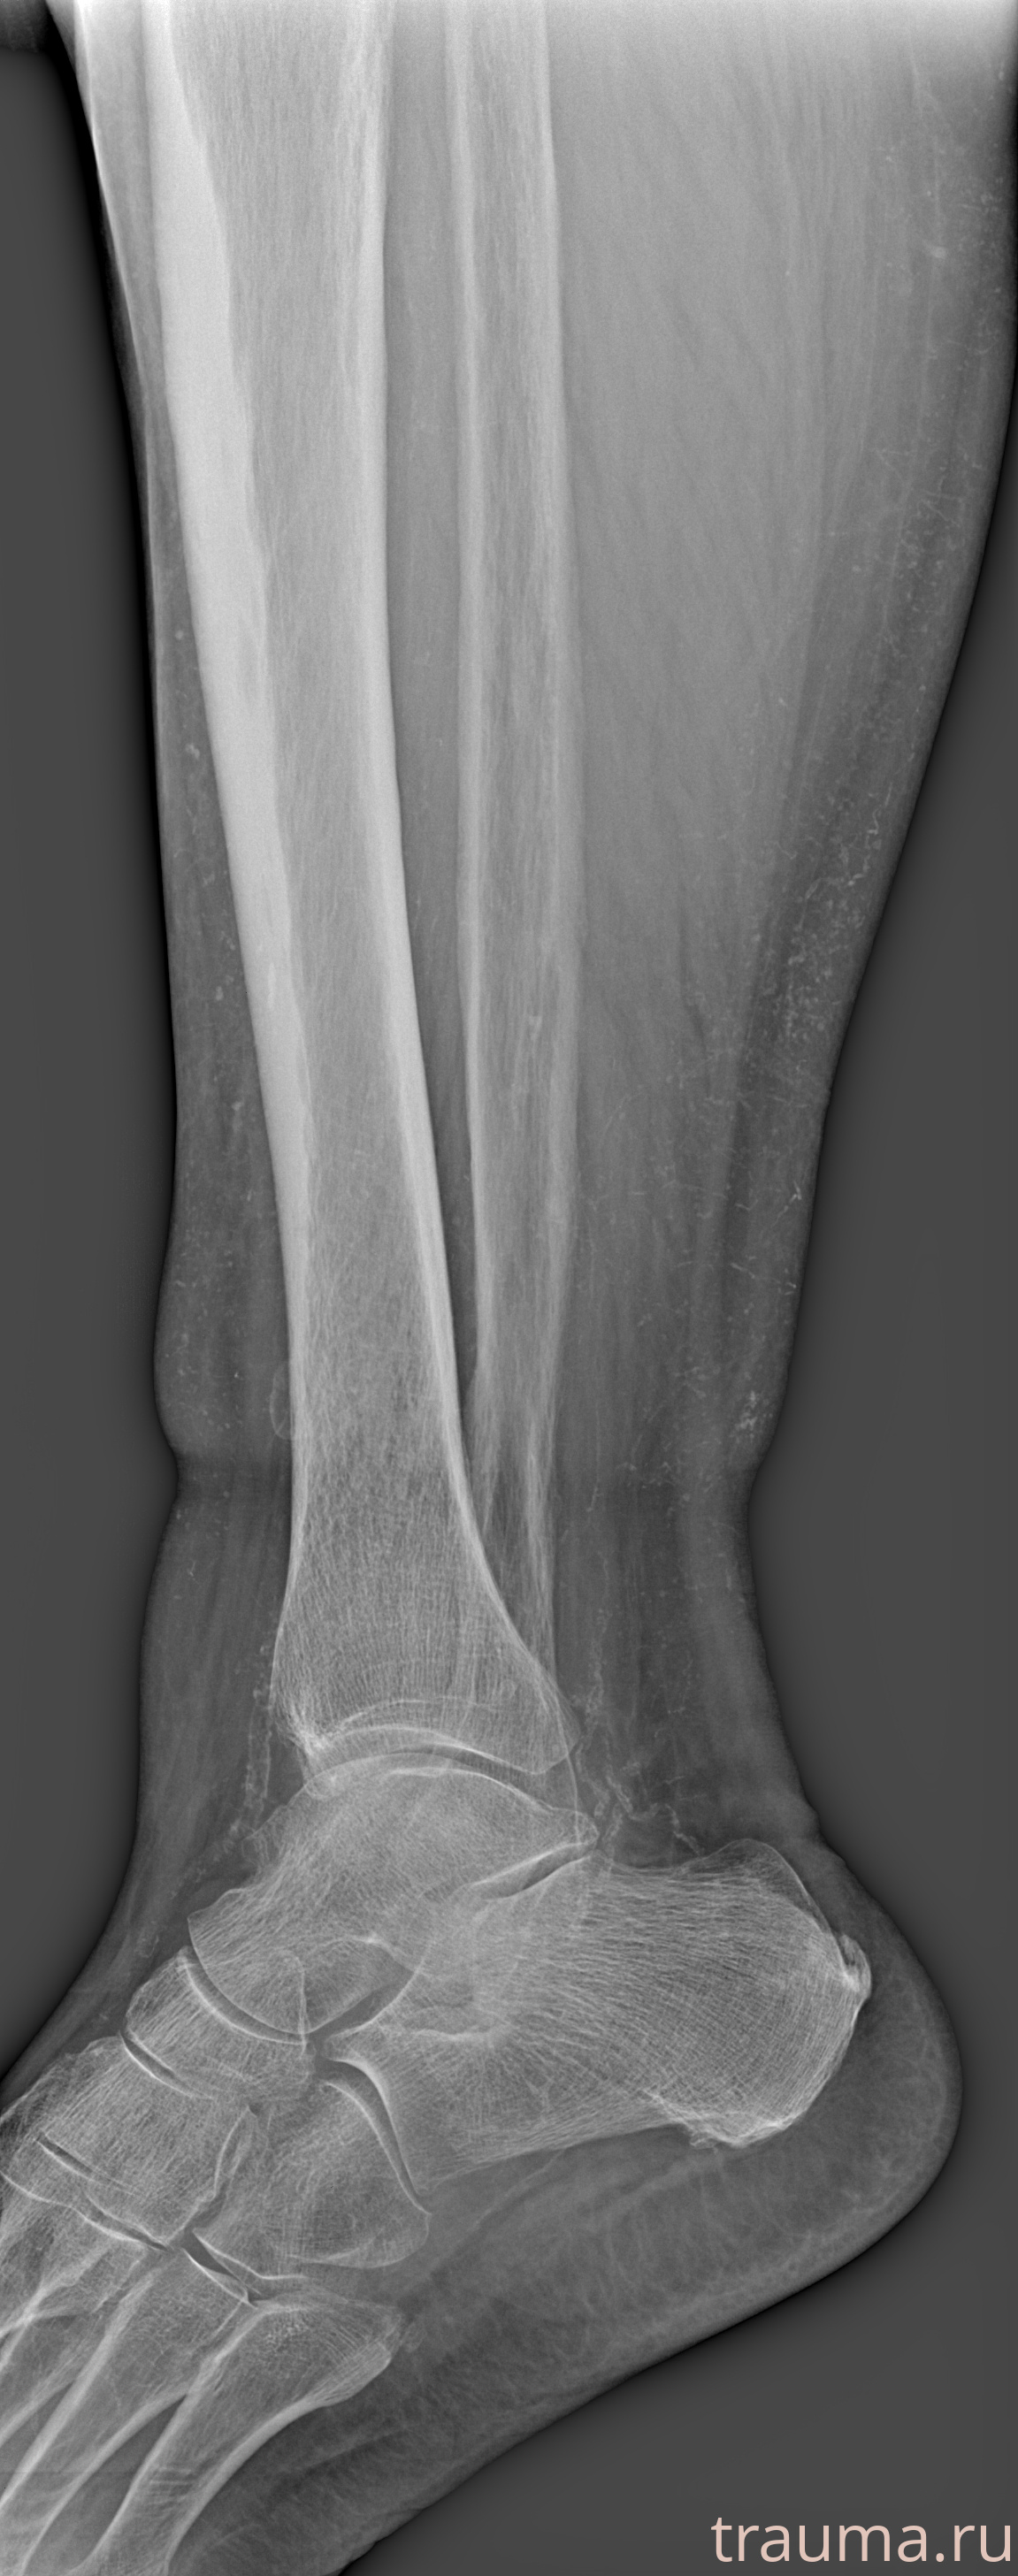

Рентгенограммы

Рентген на дому: по вашему адресу приезжает врач-рентгенолог, травматолог-ортопед с мобильным рентгеновским аппаратом, проводит диагностику травмы или заболевания, делает необходимые рентгенограммы, дает рекомендации по дальнейшему лечению. Получить качественные снимки в домашних условиях возможно благодаря уникальной методике, разработанной МосРентген Центром для института  Склифосовского